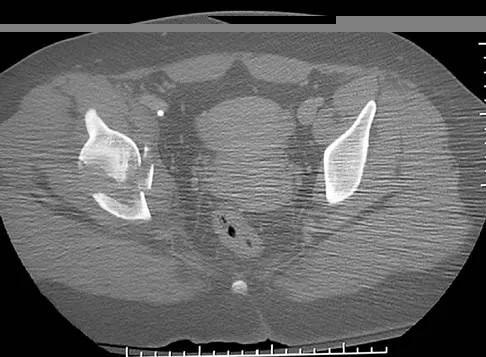

Figures 22a and 22b show the radiographs of a patient who reports stiffness of the hip and associated pain. Management should consist of

The patient has grade IV heterotopic ossification with the limb in an abnormal nonfunctional position. Treatment should consist of excision of the bone to restore hip motion and prophylaxis to prevent recurrent formation. The best time to excise the bone is controversial, with no conclusive evidence supporting early or late excision. Pellegrini VD Jr, Koniski AA, Gastel JA, Rubin P, Evarts CM: Prevention of heterotopic ossification with irradiation after total hip arthroplasty: Radiation therapy with a single dose of eight hundred centigray administered to a limited field. J Bone Joint Surg Am 1992;74:186-200.

- Warren SB, Brooker AF Jr: Excision of heterotopic bone followed by irradiation after total hip arthroplasty. J Bone Joint Surg Am 1992;74:201-210.